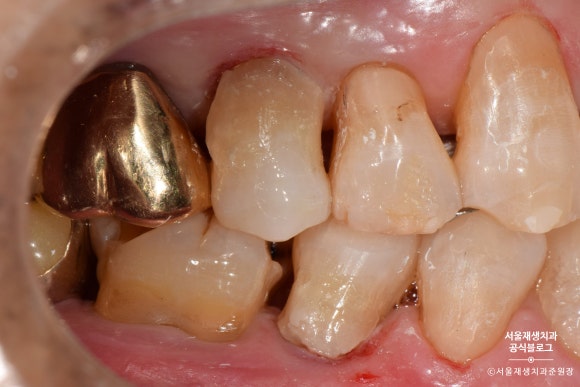

짠!

완성되었습니다.

치아와 잇몸의 경계부위를 때우기 때문에,

깔끔한 마무리를 위해 잇몸쪽으로 기구 손질을 많이 하게 됩니다.

잇몸 가장자리가 빨개진 것은 대개 하루이틀이면 원래대로 돌아옵니다.

꼼꼼한 치료의 결과라고 생각해주시면 됩니다^^